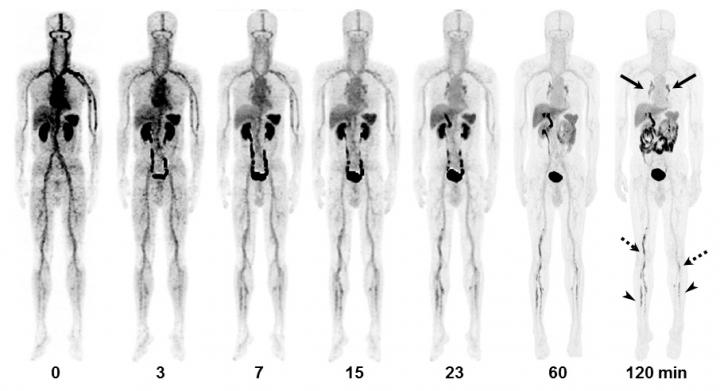

A first-in-human study featured in the February issue of The Journal of Nuclear Medicine reports that the novel positron emission tomography/computed tomography (PET/CT) tracer 18F-GP1 showed excellent image quality and a high detection rate for the diagnosis of acute venous thromboembolism (VTE). Well-tolerated in patients, 18F-GP1 PET/CT also identified blood clots in distal veins of the leg below the knee, where conventional imaging has limitations.

Upon image review, researchers found that 18F-GP1 uptake in thromboemboli was easily distinguishable from the blood pool. Moreover, a positive correlation was observed between 18F-GP1 uptake and P-selectin expression on circulating platelets, which shows the presence of activated platelets and acute VTE. 18F-GP1 PET/CT detected thromboembolic foci in all 20 patients with deep-vein thrombosis or pulmonary embolism. Additionally, 18F-GP1 PET/CT showed an increased uptake in the distal veins of the leg in 12 patients that was not detected with conventional imaging.